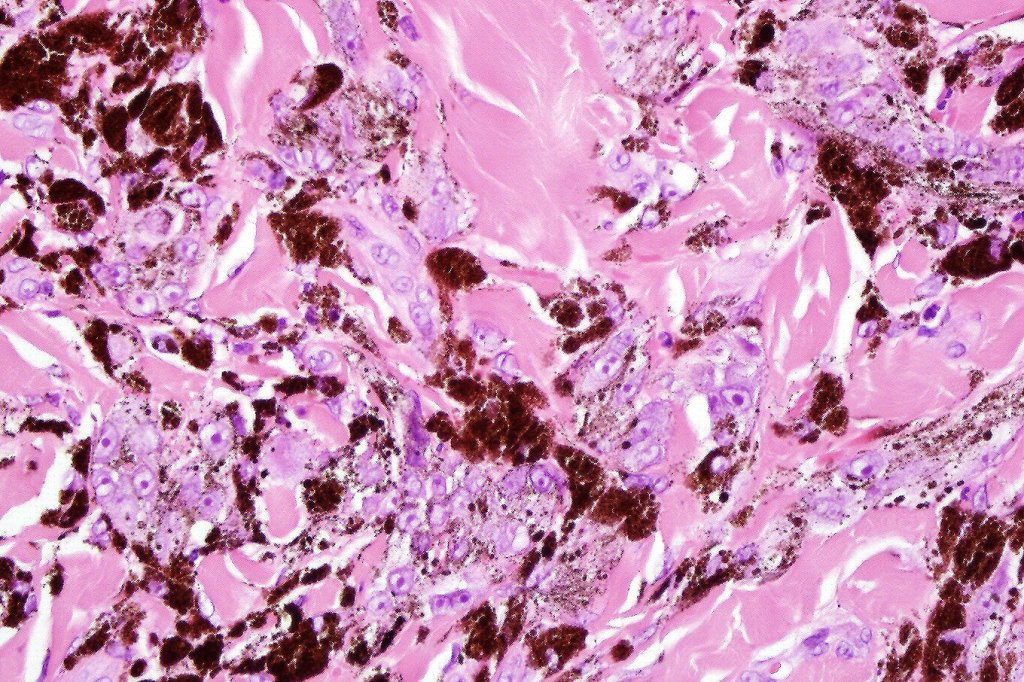

•Composed of an admixture of large epithelioid melanocytes with vesicular nuclei containing a very prominent nucleolus (fried egg cells), spindle cells, dendritic cells & melanophages

•The epithelioid cells are typically very uniform

•Few mitoses